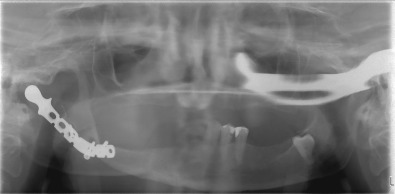

TMJ imaging of the appropriate nature and quality is fundamental for diagnostic evaluation and treatment planning in the TMJ patient. Although conventional imaging (such as panoramic radiography) is cost-effective and with lower radiation exposure compared to more advanced imaging modalities, it only provides two-dimensional detail. With superimposed regional anatomy over the region of interest, it is often necessary to take films in different planes to accomplish the detail required for diagnostic and planning purposes. For this reason, coupled with the potential for artefacts and other processing errors, conventional radiology is not the primary choice for TMJ imaging when considering secondary TMJ reconstruction where greater imaging accuracy and detail is required. However, conventional imaging or plain film still remains a useful initial study.

Computed tomography (CT ) permits detailed assessment of the TMJ, allowing views in the axial, coronal, and sagittal planes and also makes 3D volumetric reconstruction possible. CT is particularly useful in the assessment of bony structures and pathologies such as TMJ ankylosis. Indeed a “bony window” setting helps accentuate this effect, while a “soft-tissue” setting helps visualize nonosseous structures more clearly. However, despite the latter, the TMJ disk and other soft tissue structures in the region of interest are often impossible to view with CT alone. Higher radiation exposure and cost can be brought down considerably with the use of cone beam computed tomography (CBCT) technology but image artefacts from metallic objects, whether dental restorations or metallic prostheses near or in the field of interest, produce a starburst pattern of scatter. This may mask the detail required for TMJ assessment and other image modalities may be sought. Magnetic resonance imaging (MRI) is widely accepted as the study of choice to visualize the TMJ disk and ligaments, adjacent soft tissues, inflammatory changes, and the presence of joint effusion. Depending on image weighting, two commonly used studies are T1 images, which are fat-enhancing and provide excellent anatomic detail such as disk position/displacement, and T2 imaging, which is used in identifying inflammatory processes and/or the presence of joint effusion in the TMJ. Open and closed views (see Fig. 3.10.3 ) are captured to understand changes in joint biomechanics and disk pathology. As with CT imaging, artefacts can occur with metallic objects such as dental restorations. Aneurysmal brain clips or patients with indwelling cardiac pacemakers are contraindications for MRI study. Volumetric 3D reconstruction is also not easily achievable unlike with CT imaging, however Costa et al. conducted a study to define the diagnostic value of a method for 3D reconstruction of MRI images for the assessment of TMJ and found the method to be a useful and an accurate tool for this purpose, particularly when focusing on internal derangement.